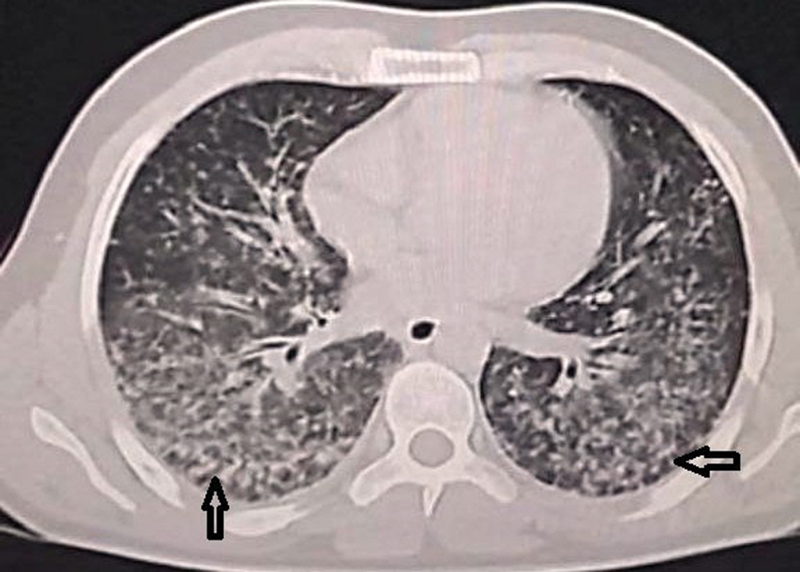

本病例报告介绍了一例中年男子,他经历了罕见和严重的水痘感染,发展为水痘肺炎和罕见的深静脉血栓形成并发症,以及随后的肺栓塞。尽管具有免疫功能,但患者的水痘感染导致了一个非典型和复杂的临床过程。患者最初表现为水疱疹、发热和疲劳,随后发展为严重缺氧和呼吸困难。影像学表现为双侧弥漫性结节实变,符合水痘肺炎。虽然水痘肺炎有很好的文献记载,但它在免疫能力强的个体中并不常见。在水痘感染的情况下,这是非常罕见的,特别是在没有免疫缺陷和没有其他危险因素的情况下,在男性患者中。该病例强调了在健康个体中保持高临床怀疑指数以及时诊断和治疗与水痘感染相关的可能危及生命的并发症的重要性。关键的学习要点包括早期识别和干预以减轻严重并发症的必要性,水痘肺炎患者可能需要血栓预防,并建议水痘肺炎患者可能需要血栓预防以预防血栓事件。

This case report presents the case of a middle-aged man who experienced a rare and severe presentation of varicella infection, with the development of varicella pneumonia and the rare complications of deep venous thrombosis, and a subsequent pulmonary embolism. Despite being immunocompetent, the patient's varicella infection resulted in an atypical and complex clinical course. The individual initially presented with a vesicopustular rash, fever, and fatigue, which progressed to severe hypoxia and dyspnea. Radiological findings revealed diffuse bilateral nodular consolidation consistent with varicella pneumonia. Although varicella pneumonia is well documented, its occurrence in immunocompetent individuals is uncommon. In the context of varicella infection, it is very rare, particularly in the absence of immunodeficiency and with no other risk factors, in a male patient. This case underscores the importance of maintaining a high index of clinical suspicion to promptly diagnose and treat potentially life-threatening complications associated with varicella infection in otherwise healthy individuals. Key learning points include the necessity of early recognition and intervention to mitigate severe complications and the potential need for thromboprophylaxis in varicella pneumonia patients and suggests the potential need for thromboprophylaxis in patients with varicella pneumonia to prevent thrombotic events.